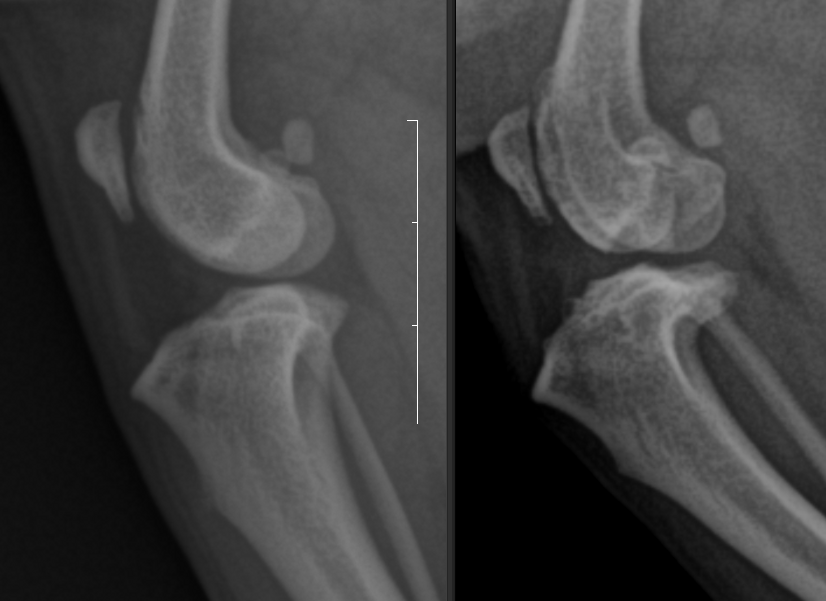

7세 CM 몰티즈, 양측성 슬개골 탈구가 있는 개.

4년 전 심한 슬개골 탈구를 보이며 좌측 후지 파행을 보여 보호자가 좌측 후지만 수술하기로 결정.

이후 우측 파행은 관찰되지 않아 수술을 하지 않음